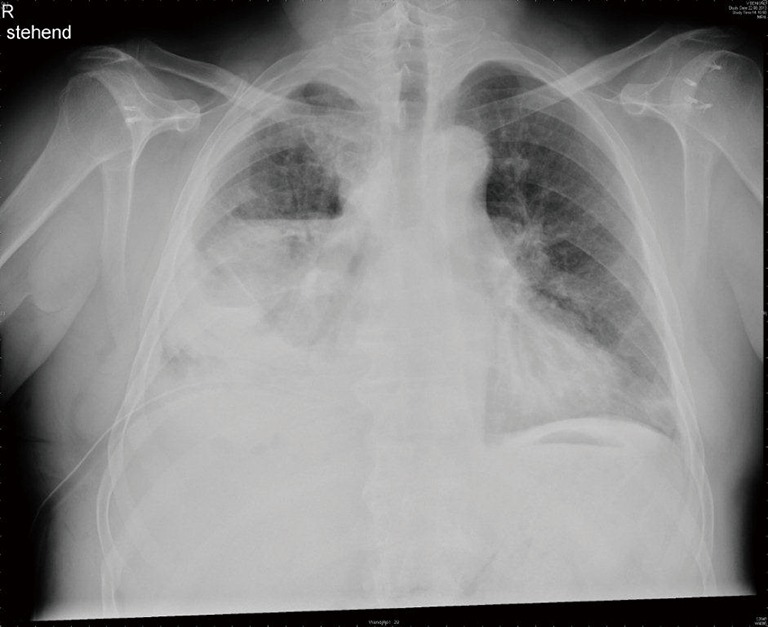

Figure 1.

Typical chest X-ray of advanced parapneumonic empyema on the right side.